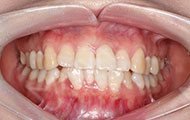

在主任的建议下拔了牙,根据我的牙齿情况,主任做了适合我的矫牙方案。选择了时代天使双膜矫治器,矫治器是透明的,可以自行摘戴,满足了我想矫正又怕丑的要求,让我在别人不知道的情况下,拥有整齐的牙齿,在矫正之前是可以在计算机上模拟显示整个矫治过程中牙齿的变化过程,可以很直观的看到,让我自己感觉心里很放心,经过一个月的等待,终于戴上了牙套,给主任和麦芽点赞!

2017-12-1不让自己留遗憾,我与歪牙要打持久战

经过朋友良心推荐,最终选择了麦芽口腔。在麦芽是张超主任给我检查的牙齿,然后跟着医助拍的片,这期间都有专人负责,张主任很专业的为我定制了方案,当天就取了牙模~